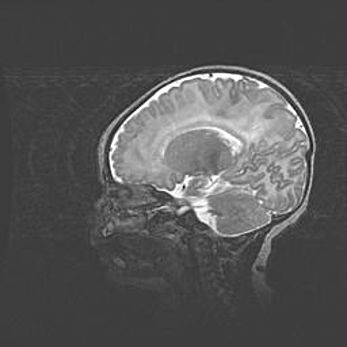

Церебральная ишемия II.

Возраст: 5 дней

Вес: 3400 г

Пол: женский

Окружность головы: 35 см

Срок гестации: 39 недель

Церебральная ишемия – это заболевание, характеризующееся недостаточностью (гипоксией) либо полным прекращением (аноксией) снабжения мозга кислородом по причине закупорки одного или нескольких сосудов. Это приводит к  что метаболическим расстройствам различной степени тяжести в тканях головного мозга, развитию коагуляционных некрозов и гибели нейронов.